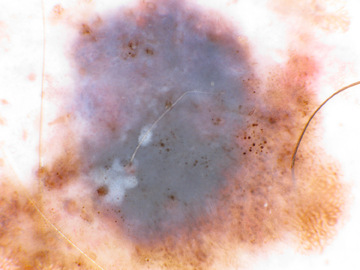

Case: 33